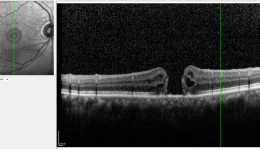

• 糖尿病性眼病:高血糖对眼睛的危害

糖尿病性眼病:高血糖对眼睛的危害

糖尿病作为现在最常见的慢性疾病之一,危害不止于血糖异常,更会悄悄损伤全身血管,眼底便是重灾区。数据显示,糖尿病患者患病10年以上,眼部并发症发生率超50%,我们往往因忽视早期信号而最终面临失明风险。其实,我们可以通过了解这些,来保护我...